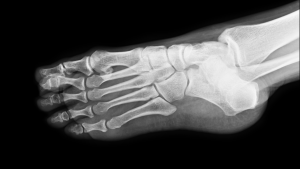

How Imaging Helps Identify Ankle Injuries

When ankle pain, swelling, or bruising persists, imaging is often necessary. X-rays help determine whether a bone is cracked, displaced, or fully broken and play a key role in diagnosing ankle sprains and fractures that may not be obvious during a physical exam.

In some cases, advanced imaging may be recommended to assess ligament damage or subtle fractures not fully visible on standard X-rays.